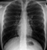

Mitral valve replacement

- This is a 'scout view' (planning view) for a chest CT scan

- Midline sternotomy wires (red ring)

- Mitral valve replacement (arrowhead)